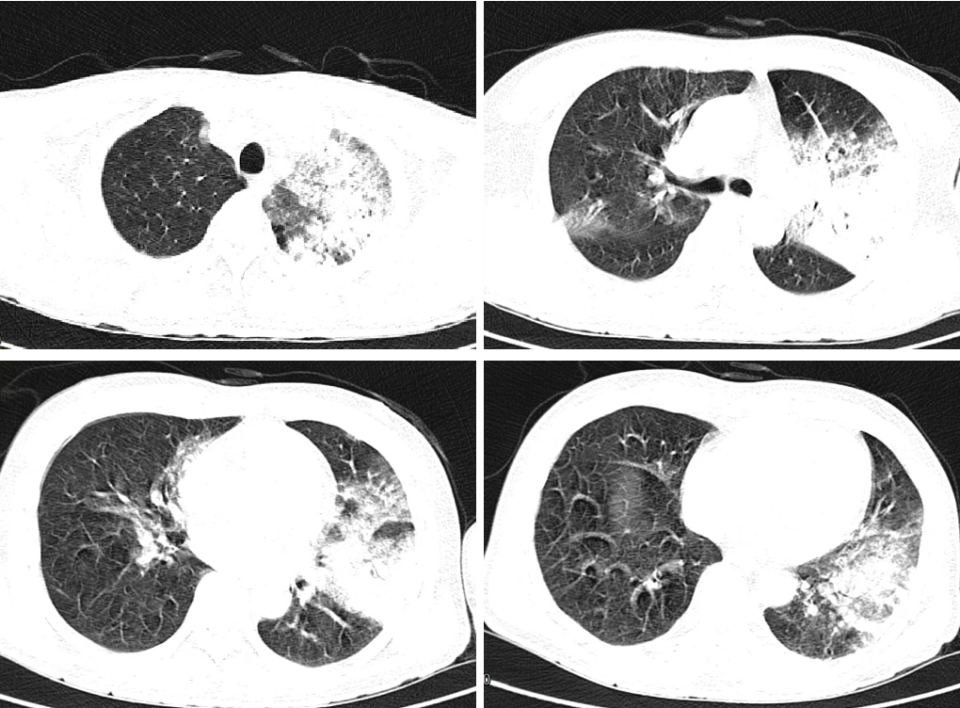

81 岁老年男性,原有慢阻肺病、支气管扩张史,因咳嗽气喘加重伴发热 1 周入院,CT 示支扩伴感染、肺大泡(图 2)。

图 2 入院 CT 示示支气管扩张伴感染、肺大泡,肺结构扭曲破坏。

入院后予哌拉西林/他唑巴坦、全身性激素、雾化 SABA/SAMA/ICS 等治疗咳嗽好转,热退,但入院第 5 天又发热,咳嗽气喘加重,遂予气管镜检查,BALF mNGS 检查。